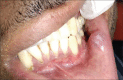

'Hibernoma' is a neoplasm that arises from vestiges of fetal brown fat, and its occurrence in oral cavity is extremely rare. Its most common locations include thighs, the inter-scapular region, and the cervical region. In the present case, a 37-year-old male patient reported to our department with a localized swelling on his lower left labial mucosa along with multiple cutaneous well-defined swellings on his right arm and abdominal region. Incisional biopsy was carried out. Histopathological examination revealed sheets of multi-vacuolated eosinophilic cells with the granular cytoplasm interspersed with fat cells suggestive of oral hibernoma. These are rare lesions and could be often a missed-out diagnosis. Therefore, it is imperative to consider oral hibernoma among the commonly considered differential diagnosis of oral mucosal swellings.